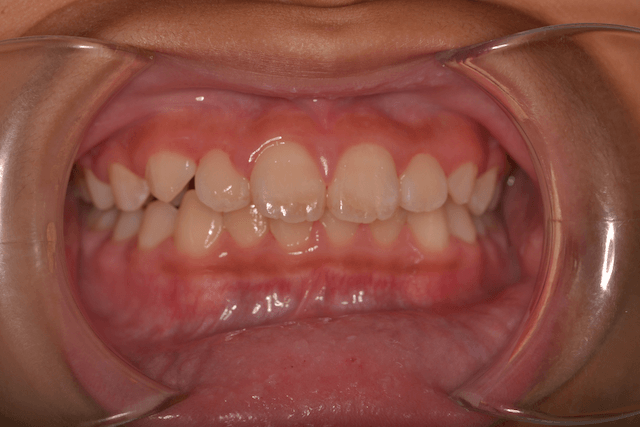

過蓋咬合を床矯正装置、下顎骨の前下方成長の促進で改善した症例

患者情報

11歳男性

主訴

咬み合わせを直したい

行った治療内容

床矯正装置、下顎骨の前下方成長の促進

治療のリスク

使用時間が短いと効果でない

治療期間

動的治療期間1年6か月

※ クリックして拡大することができます。